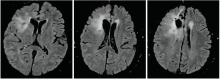

林辉(放疗科住院医师):病史汇报(略)。患者术后于2008-09-12在我科行术后单纯放疗(三维适形放疗), 56 Gy/28 F, 2 Gy/(F· 天)。患者放疗结束后未遵医嘱返院复查, 在当地不规律复查。2015年突发意识丧失伴肢体抽搐2次, 2016-06-15在汕头中心医院复查头颅MRI平扫+增强提示右额叶胶质瘤复发, 见图2图3

图2 2016-06-15 MRI(T1-C+)图像

图3 2016-06-15 MRI(T2-FLAIR)图像